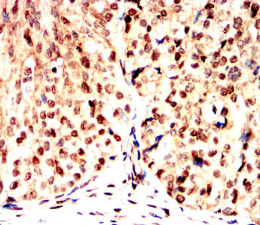

GMNN Mouse Monoclonal antibody[1H11G]

This gene encodes a protein that plays a critical role in cell cycle regulation. The encoded protein inhibits DNA replication by binding to DNA replication factor Cdt1, preventing the incorporation of minichromosome maintenance proteins into the pre-replication complex. The encoded protein is expressed during the S and G2 phases of the cell cycle and is degraded by the anaphase-promoting complex during the metaphase-anaphase transition. Increased expression of this gene may play a role in several malignancies including colon, rectal and breast cancer. Alternatively spliced transcript variants have been observed for this gene, and two pseudogenes of this gene are located on the short arm of chromosome 16.

Immunogen:    Purified recombinant fragment of human GMNN (AA: FULL 1-209) expressed in E. Coli.

IHC    1/200 - 1/1000